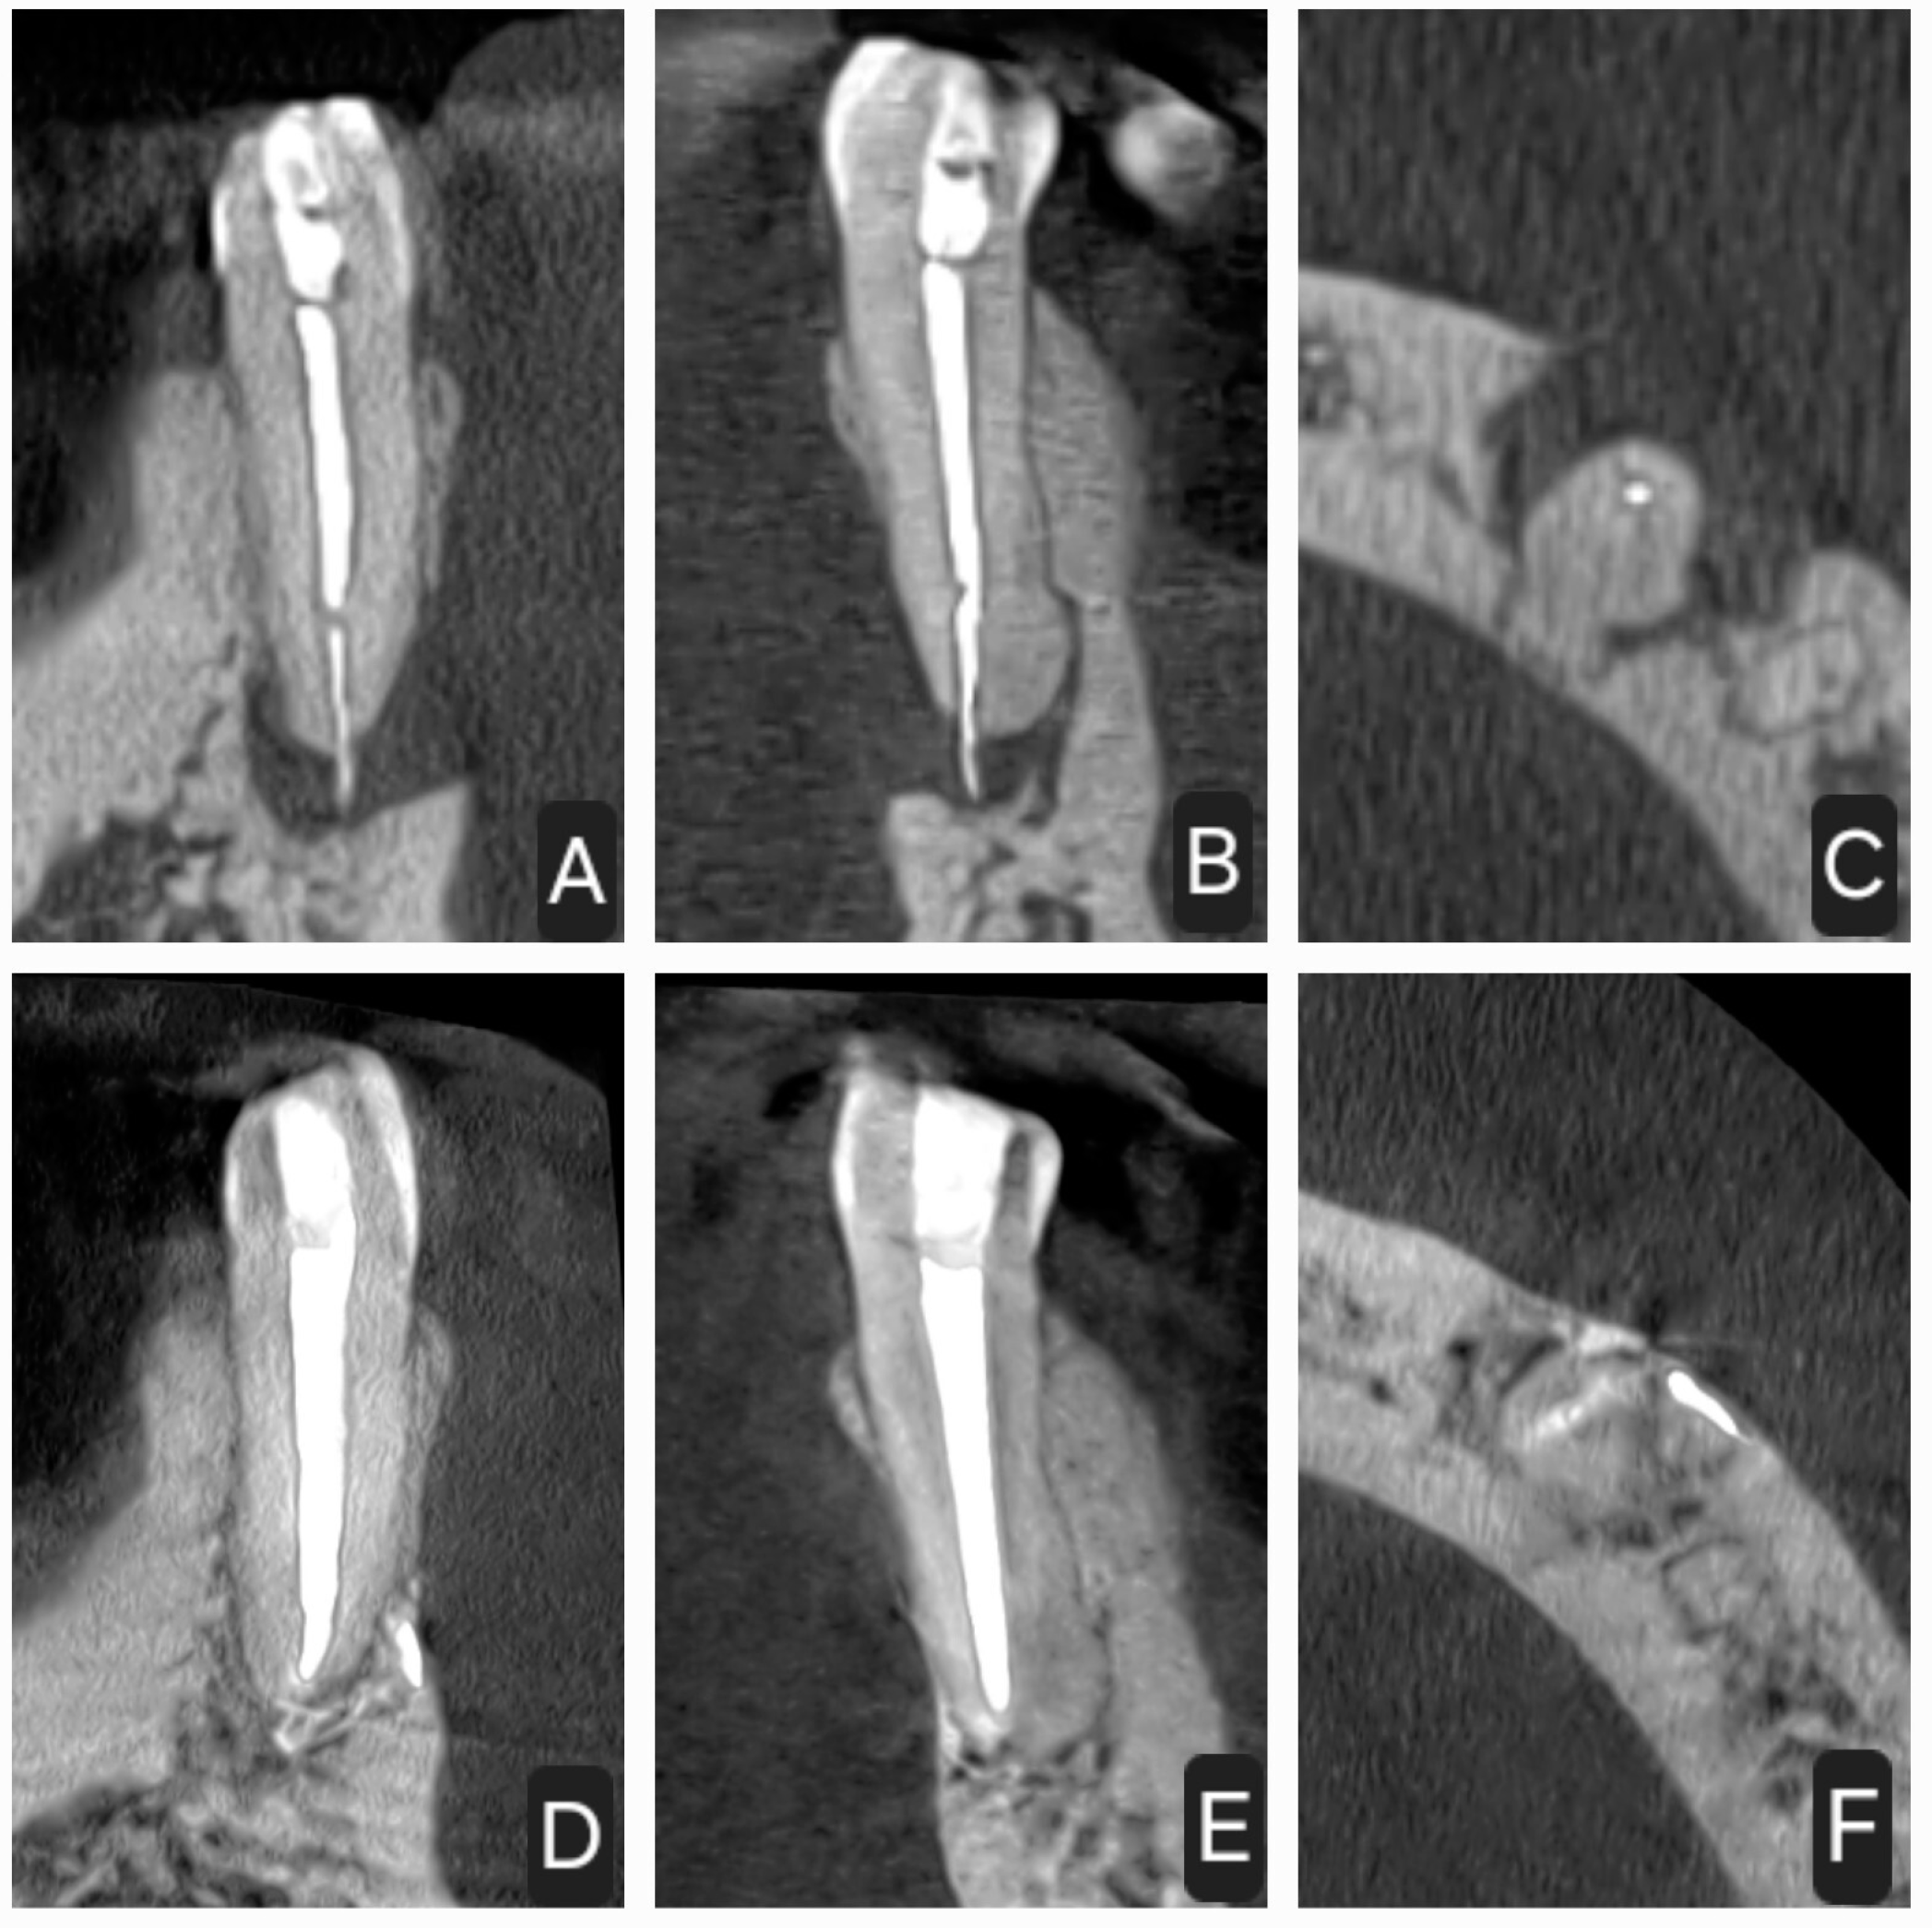

2.1. First Case

2.2. Second Case

2.3. Third Case

2.4. Fourth Case

2.5. Fifth Case